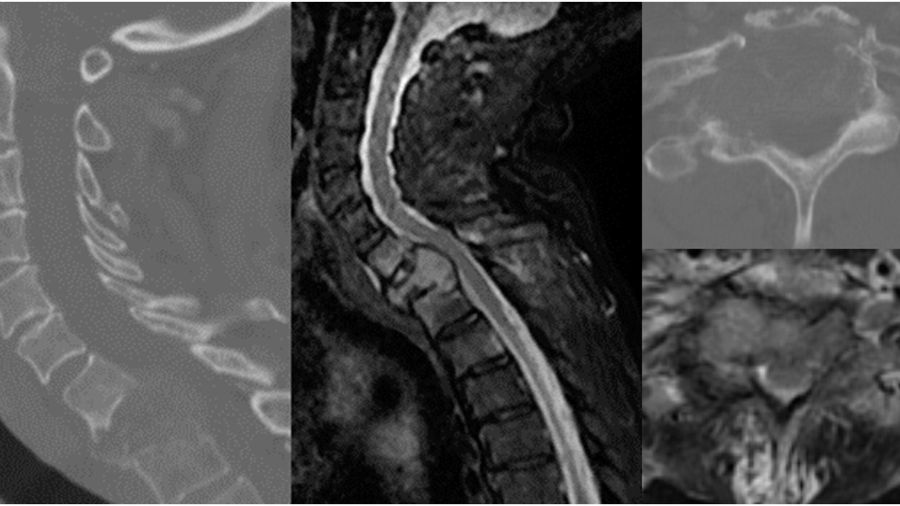

Case 2: A 71-year-old man presents with one week of back pain.

He was diagnosed 5 months ago with NSLC adeno-carcinoma also with an EGFR mutation and started on osimertinib. He has progressed through targeted therapy and recently started chemotherapy.

One month ago, he was found to have metastases to the liver and pelvis and was started on pembrolizumab/ carboplatin/ pemetrexed. He is now found to have an L2 pathologic fracture with retropulsion. He is ambulatory and full strength. His ECOG performance status is 2 and his SINS is 15. The patient seems to have progressed through targeted therapy but just started chemotherapy recently, which still leaves room for further systemic options.

Patient is offered separation surgery plus stabilization.